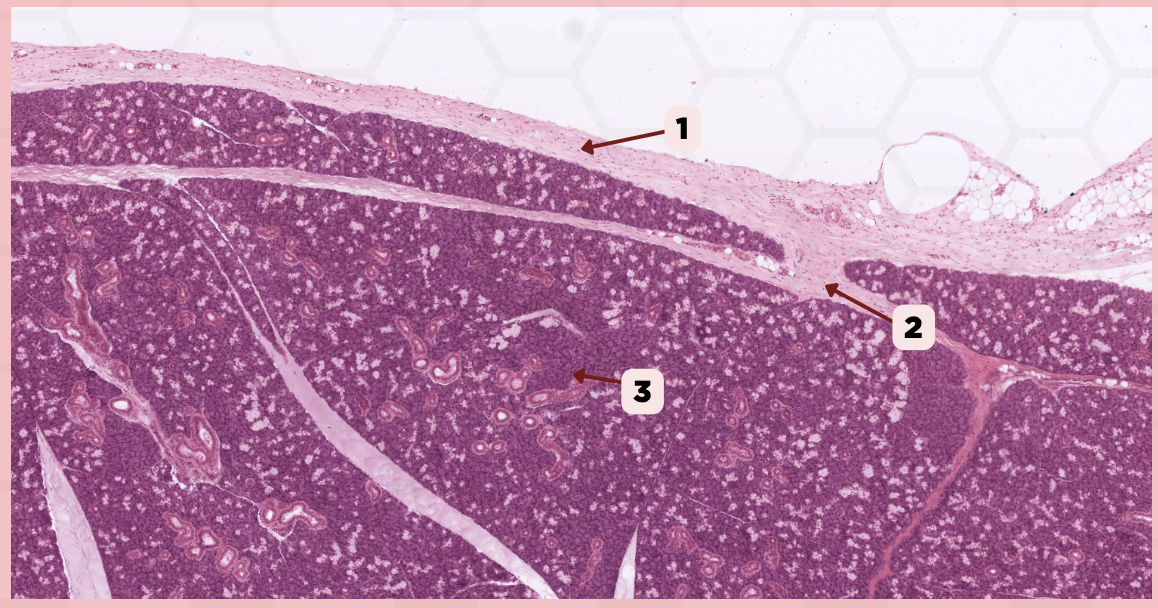

Lip

What specimen is being showed in this picture?

Keratinized Stratified Squamous Epithelium (Epidermis)

Identify the structure labeled as 1.

Mucocutaneous Junction

Identify the structure labeled as 1.

Lip

What specimen is being showed in the picture?

Epidermis

Identify the structure labeled as 1.

Dermis

Identify the structure labeled as 2.

Arrector Pilli Muscle

Identify the structure labeled as 3.

Hair Follicle

Identify the structure labeled as 4.

Sebaceous Glands

Identify the structure labeled as 5.